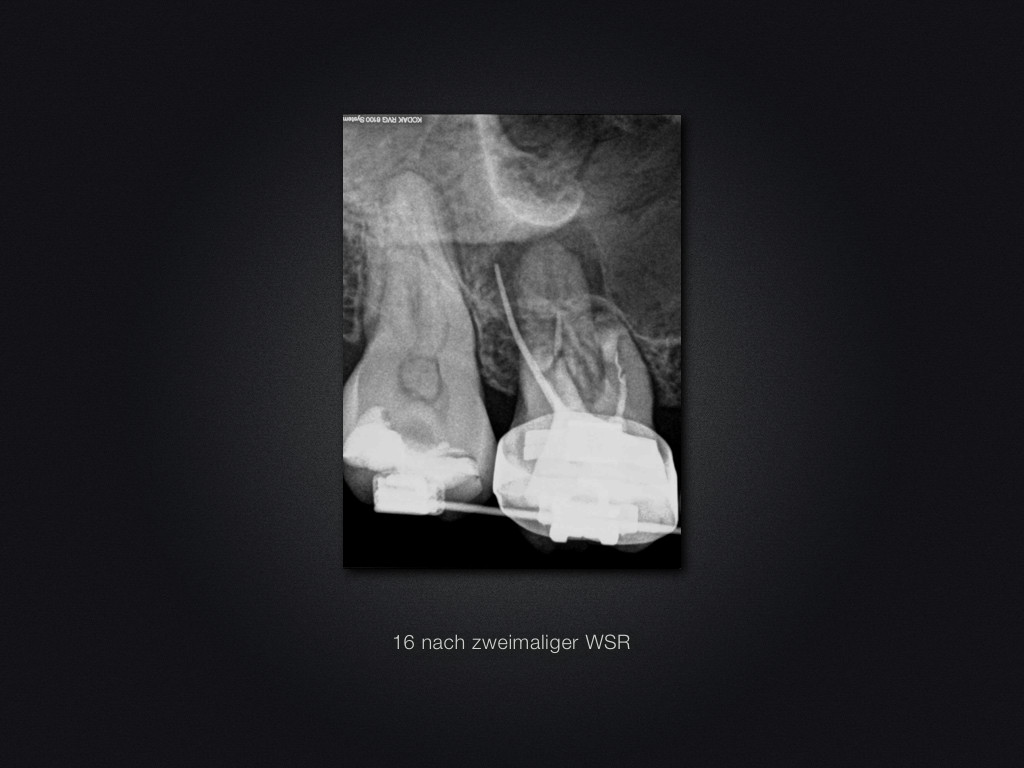

Saving Hopeless Teeth (XXX)